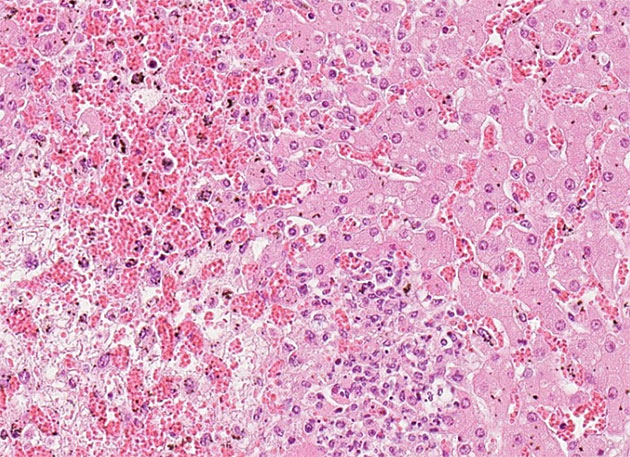

Bei der feingeweblichen (pathohistologischen) Untersuchung können ausgeprägte nekrotisierende, entzündliche Herde in den betroffenen Geweben festgestellt werden. Die Herde finden sich in erster Linie in der Leber und in geringerem Maße in Darmtrakt und Herzmuskel. Der Erreger kann mittels einer Spezialfärbung (Versilberung durch Warthin-Starry oder Giemsa-Färbung) nachgewiesen werden. Hierbei lassen sich die intrazellulären, filamentösen Bakterien von dem umliegenden Gewebe durch eine Silberfärbung differenzieren.

Abbildung 1. Pathohistologisches Bild der massiven Leberzellnekrose; rechts im Bild nur leicht veränderte Leberzellen; links im Bild hochgradig nekrotische Zellen mit Abräumreaktion und starker Einblutung. HE, 20x

Bei der Sektion fielen ein ausgeprägter allgemeiner Ikterus, Blutungen in verschiedenen Organen und pathomorphologische Veränderungen in der Leber und im Darmtrakt auf. Die feingewebliche Untersuchung ergab massive multifokale Lebernekrosen sowie Nekrosen in der Herzmuskulatur und im Darm. Der Vorbericht und die pathologischen Befunde legten den Verdacht der Tyzzer-Krankheit nahe. Daher wurde die histologische Warthin-Starry-Spezialfärbung im Lebergewebe angewendet, um die obligat intrazellulären Bakterien nachzuweisen. Diese deckte eine massenhafte Ansammlung von intrazellulären, filamentösen Bakterien in der Nähe der Nekroseherde auf, typisch für Cl. piliforme.